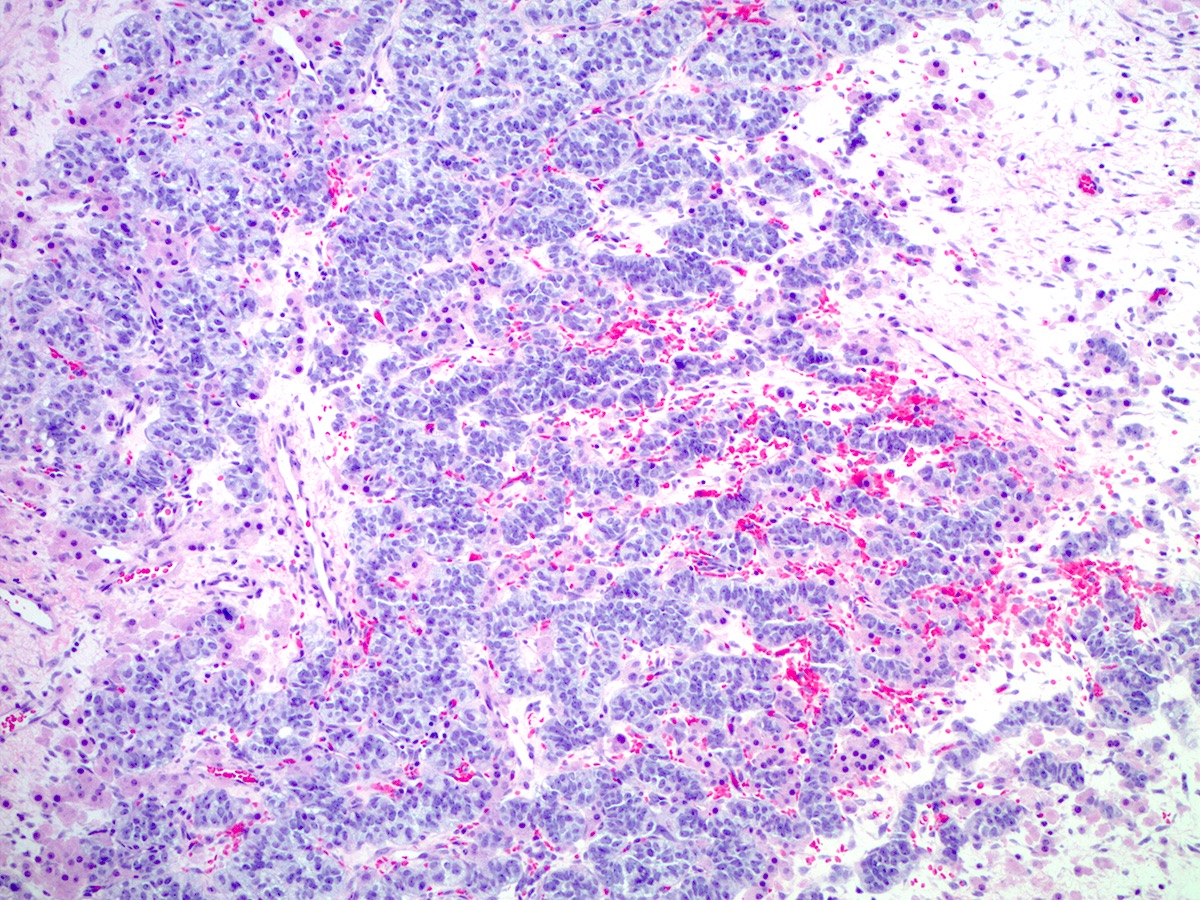

Microscopic (histologic) description

- Poorly differentiated

- Diffuse sheets of immature, sarcomatoid Sertoli cells with moderate to marked nuclear atypia and only rare foci of vague cord formation

- Increased mitotic activity, up to 20 mitoses per 10 high power fields

- Leydig cells are difficult to find; a few small clusters are typically located at the periphery of tumor nodules

Microscopic (histologic) images